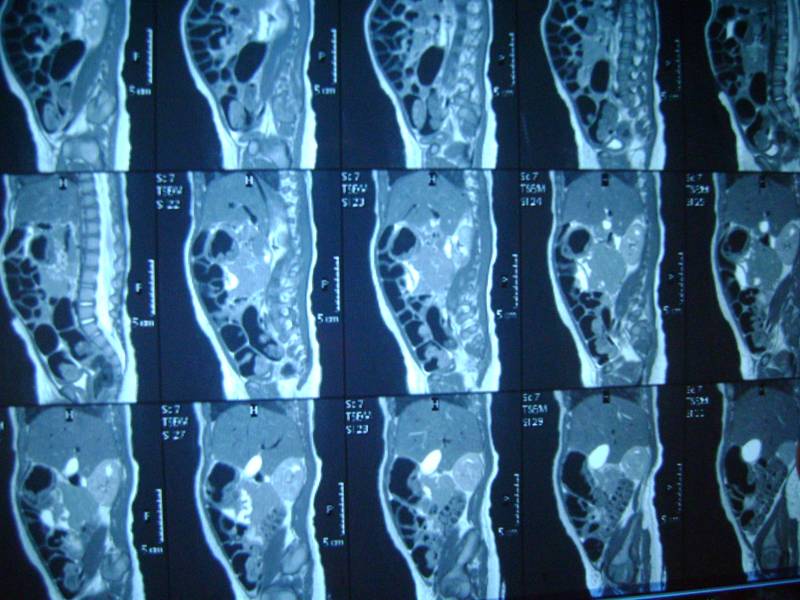

добавляем фото